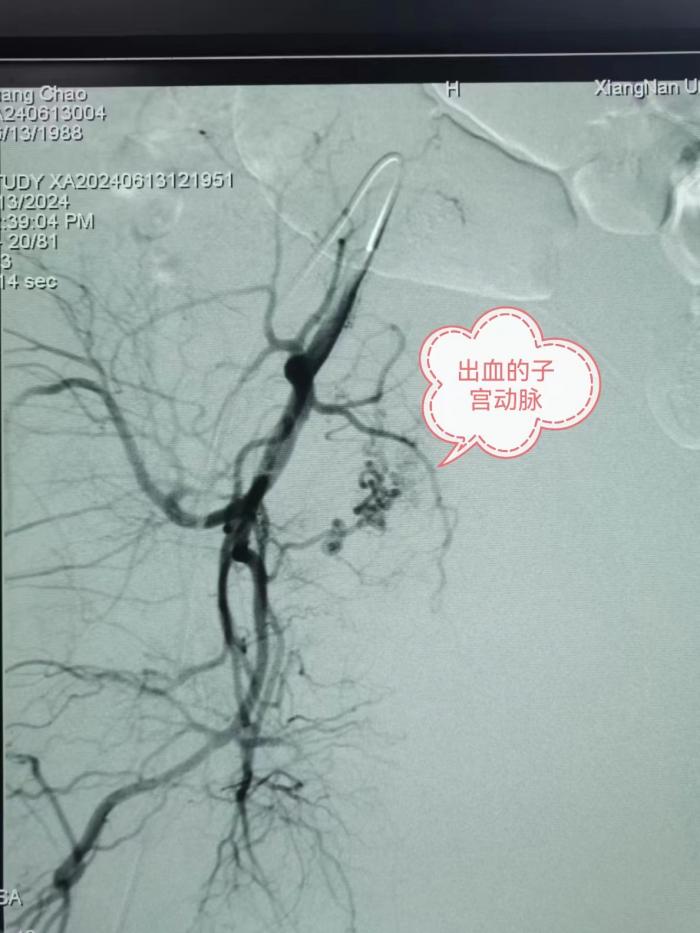

在完善相应的评估检查后,龙文兴带队护送患者进介入手术室。患者出血止不住,途经之处一路飙红,随时可能出现生命危险,龙文兴迅速进行子宫动脉造影检查,发现出血元凶,迅速对出血动脉进行了栓塞处置,患者生命体征趋入平稳。

按照常规流程,这个时候已经可以准备结束手术了,但是一贯以谨慎严谨的龙文兴却隐隐感觉还有哪里不对劲。“宫颈癌出血常见,但这种短时间这么大量出血的情况并不常见。”龙文兴说,于是他又倒回去把造影再仔仔细细的查阅了一遍。果然发现阴部内动脉一分支存在可疑,马上对可疑之血管再次进行造影检查。结果不出所料,这条并不起眼的支动脉也正在滋滋冒血。医务人员果断对这处隐匿病灶实施了栓塞,患者终于转危为安,化险为夷。“幸亏有龙医生细致谨慎,为我同时解决了两处出血点,化解了一场危机。”4天后,邝女士顺利康复出院。